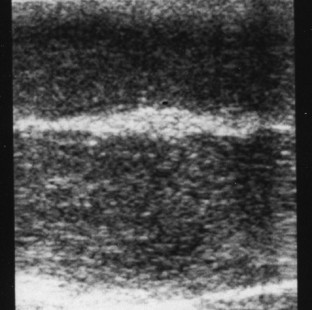

The aim of the study is to evaluate the incidence and the echographic characteristics of minimal lesions of cavernosum corpora and tunica albuginea (TA) in subjects reporting erectile dysfunction (ED), which could suggest the suspicious of La Peyronie's disease (LPD). In total, 185 patients (pts) underwent dynamic penile Ultrasound Color Doppler (USCD) for ED. None of the pts presented any clinical symptoms or any clinical findings for LPD. In this study we evaluated, using USCD, thickness, echogenicity, regularity of the surface profile of the dorsal TA, the intercavernous and the intercaverno-spongeous septa, and the extension of the eventual pathologic lesions. In all, 16 pts (8.7%) presented minimal lesions at the ultrasound examinations. In nine of these pts (56%) the lesion was localized at the dorsal position, in six (38%) on the intercavernous septum and in one patient (6%) in both positions. The dorsal lesions were represented in nodular form in four pts (4%), and in diffuse form in five pts (55%). The nodular form was present in all the intercavernous septal lesions observed. As reported in the literature, USCD represents the investigative technique of choice in the study of LPD and in ED. Furthermore, the results of this study suggest that this technique could allow the localization of minimal lesions attributable to LPD during a preclinical phase of this disease. The localization of these lesions could permit to start a therapeutic approach during an early phase of the disease.